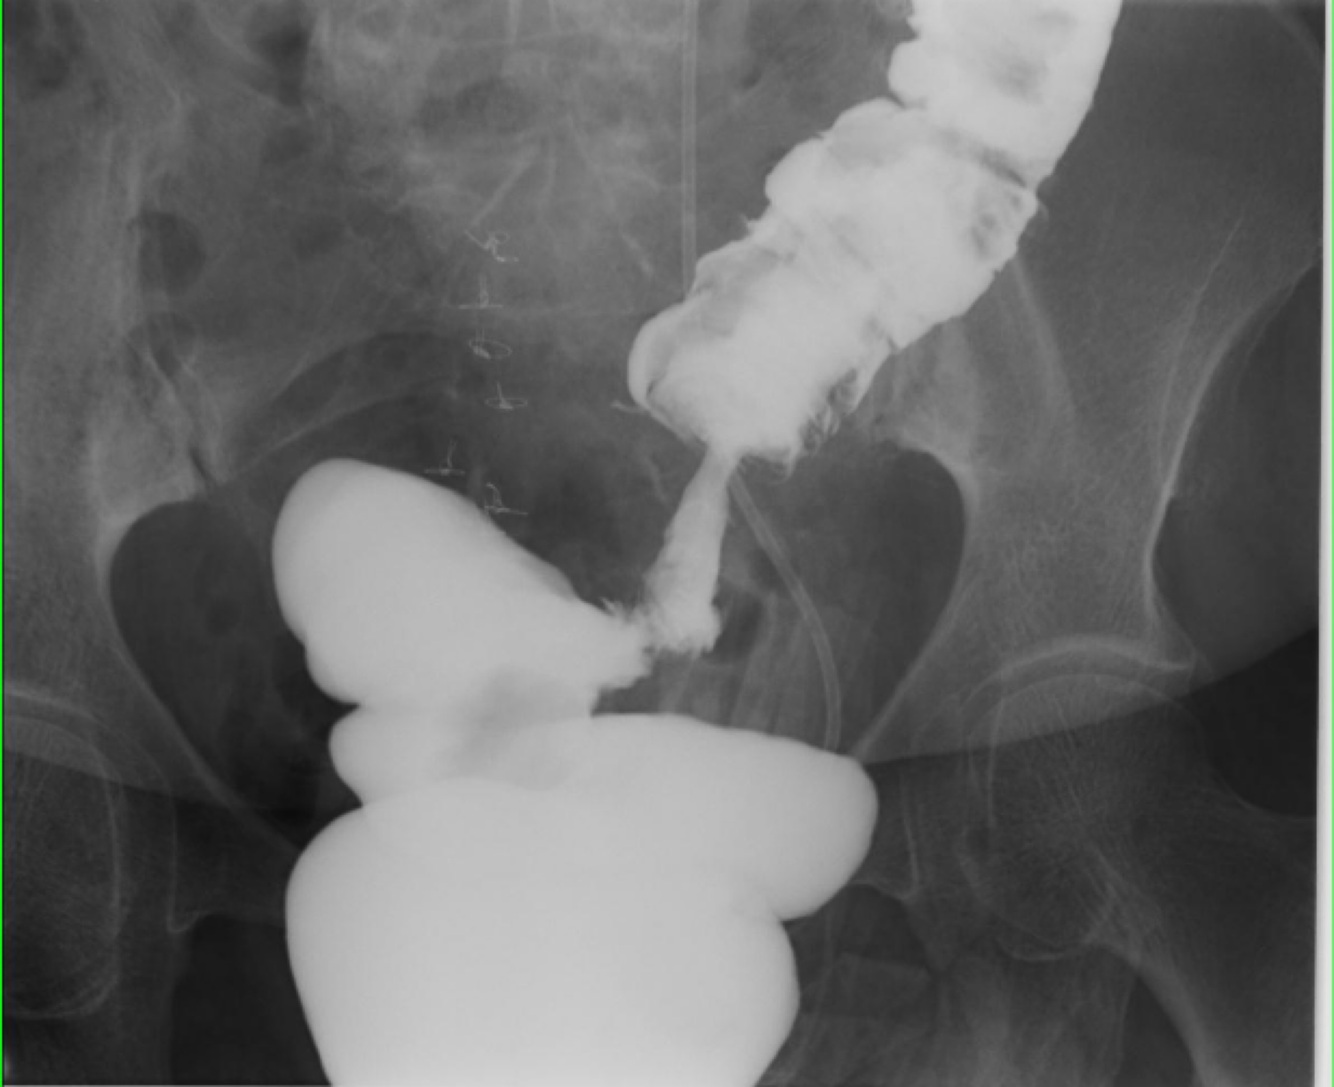

Colorectal cancer : apple core” lesion suggest a tumor in the colon.